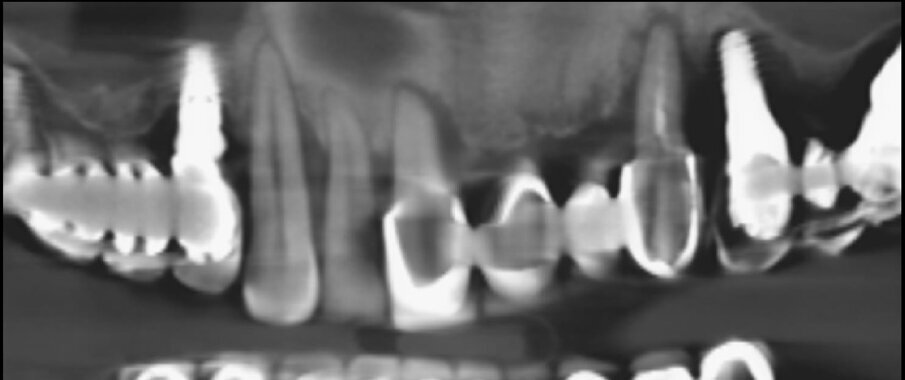

Il follow up è stato programmato con cadenza semestrale. Al momento della produzione di questo articolo, il caso è stato seguito per 18 mesi. Nell’arco di questo periodo è stata segnalata solo una complicanza di minore entità. La rottura di un angolo incisale dell’incisivo centrale, che è stata riparata direttamente alla poltrona. Dopo 18 mesi, l’ortopanoramica di controllo evidenzia una perfetta stabilità e, anzi, un miglioramento dei livelli ossei perimplantari. In particolare, a livello degli impianti ultra-short è possibile apprezzare una migliore densità ossea circonferenzialmente all’impianto e persino nella sua porzione più coronale, come è possibile apprezzare confrontando l’ortopanoramica eseguita immediatamente dopo l’intervento con quella a 18 mesi (Figg. 11a, 11b).

Fig. 11b_Confronto della qualità ossea prima e dopo 18 mesi degli impianti ultra-short inseriti a livello del mascellare superiore destro e sinistro.